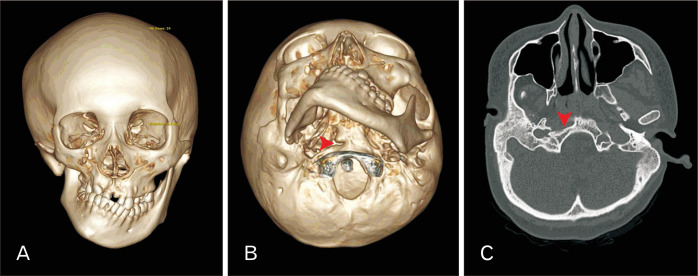

Transverse basilar cleft (TBC) is an extremely rare variation of the clivus or the basilar part of the occipital bone. In this report, a unilateral transverse basilar fissure was found at the clivus in a head computed tomography of an 18-year-old female patient diagnosed with hemifacial microsomia (HFM). Image analysis of this patient showed shortening of the ramus of the right mandible along with medial displacement of the right temporomandibular joint and hypoplastic right maxilla. In addition, observation of the clivus showed a cleft between the basioticum and basioccipital bones at the level of the pharyngeal tubercle on the right side. This cleft was identified as TBC. Clival variations, TBC included, attributed to HFM have never been reported. This report draws attention to the complex relationship between abnormal development of clivus and HFM syndrome, and sheds light on a possible genetic and molecular association between these two conditions.